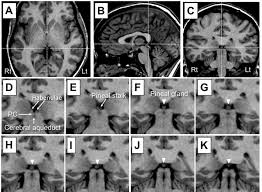

Pineal Cyst In A 6 Year Old Girl Causing Diplopia Headache And Download Scientific Diagram